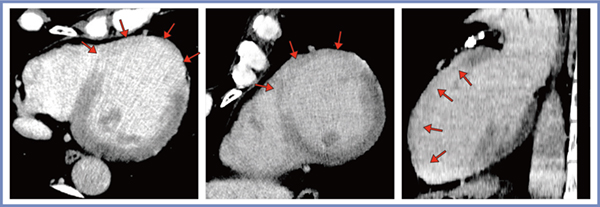

実際の症例を提示する。症例1は左室前壁の陳旧性心筋梗塞症例で,PIQEにて梗塞が高吸収域として明瞭に描出されている(図2↓)。症例2は60歳代,男性,狭心症疑い症例(図3)で,心臓CTにて左冠動脈前下行枝の高度狭窄と心尖部に構造物を認めた(a)。遅延造影CTでは,梗塞を示す白い領域の表面に黒い領域が描出され(図3 b↑),超音波検査にて心尖部の血栓が確認された(c↑)。

図2 症例1:陳旧性心筋梗塞症例のPIQEの画像